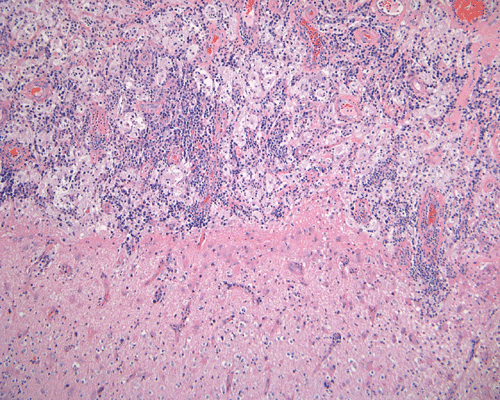

The specimen is in the form of a plaque-like, firm lesion adhered to a layer of brain parenchyma on one side (Panel A) The lesion infiltrate into the underlying brain parenchyma which leads to the formation of an irregular interphase. There is also perivascular accumulation of lymphocytes around blood vessels (Panel B  and C). On low-mangification, the lesion appears to be a mixture of lymphocytes and large cells with foamy histiocytes. The salient feature of the lesion is that of a mixture of mature lymphocytes with large to giant histiocytes (Panel D). The histopathologic picture is rather homogeneous in different parts of the lesion. On high-magnification, the large to giant histiocytes has enlarged nuclei and many of them contain engulfed lymphocytes or polymorphonuclear leukocytes (emperipolesis ) (arrows in Panel E an F).

Grossly, dural based RDD are firm, often plaque like lesions that resemble meningioma but they are firmly adhered to the brain.

Histiologically, the features of cranial RDD are similar to those occurring in the lymphnodes.  Lesions are composed of sheets or syncytia of large, pale histiocytic cells with abundant granular eosinophilic cytoplasm and ill-defined or feathery cytoplasmic borders in a lymphocytic, chronic inflammatory cell background. Extranodal sites commonly exhibit a degree fibrosis and this can obscure the visibility of the histiocytic proliferation. Nuclei of the large histiocytes vary in size and may be large, round and vesicular with smooth nuclear contours 2. A mild degree of cytological atypia is commonly seen.  Most nuclei contain a single small nucleolus, but others possess multiple nucleoli or a single prominent nucleolus. Mitotic figures are usually difficult to detect or are absent altogether. The prominent background of chronic inflammation is largely comprised of a mature plasmacytic infiltrate with interspersed lymphoid follicles 2.  Emperipolesis is consistently found in nodal disease and often is less evident at extranodal sites.  Its recognition is key to correct diagnosis.